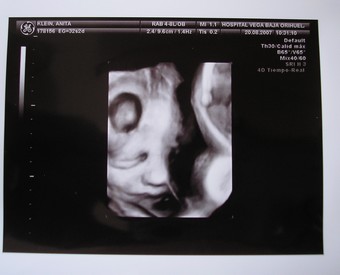

Pont nekem is az jutott eszembe,mint Móninak,hogy szinte csak most mutattad az első UH képet és már lassan szülsz...

Így elmegy 9 hónap

....